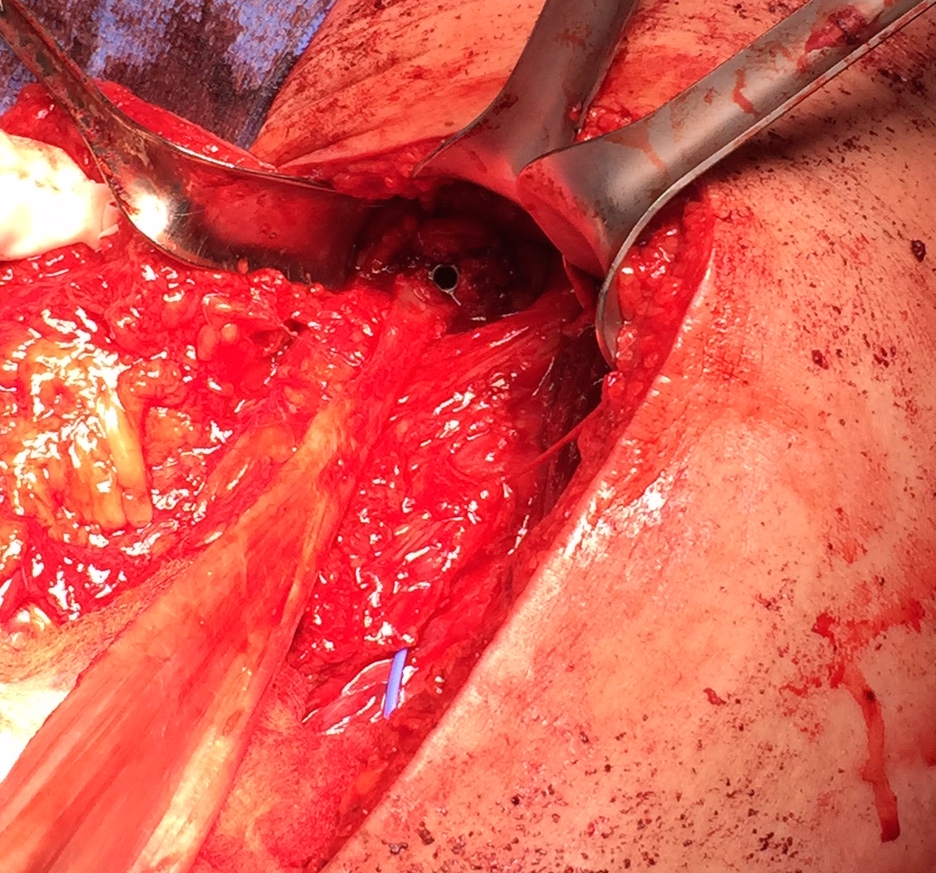

- 2 - 3 suture anchors, double loaded

Exposing ischial tuberosity (*) with Cobb retractor

Post suture anchor repair

Ischial tuberosity exposed, then achilles bone block secured with screw